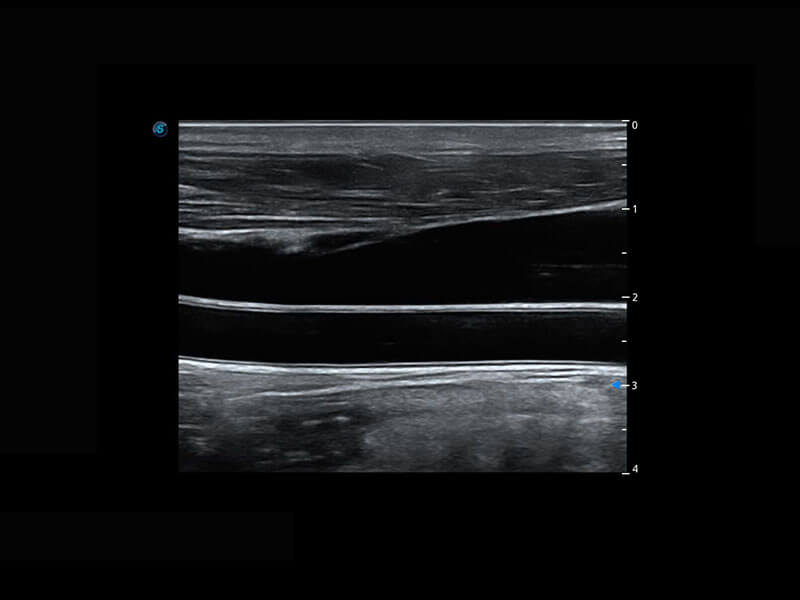

新生儿脊髓圆锥

新生儿心脏